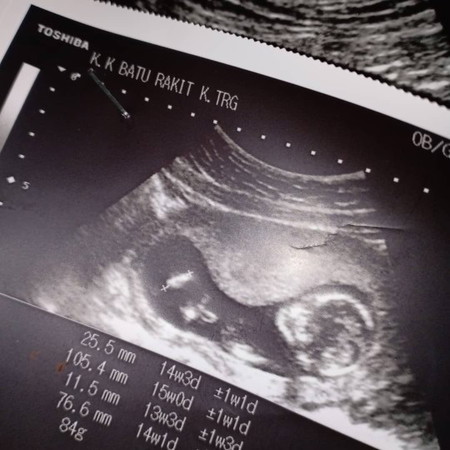

slm mummy2.. ada x pernah doc bagitau size kepala baby besar.. skrg 15minggu.. dh tnya doc.. knpa.. tapi doc juz bagitau nnti tgk balik.. scan balik 2minggu lagi.. dh 3kali scan.. harap xde pape.. doakan sy dan baby ye.. ?

Normal LA, hari tu Dr cakap berat baby kurang LA . Perut and kaki kecil LA, baby akan berkembang elok juga . skg alhamdullilah tinggal tunggu Hari nak bersalin.